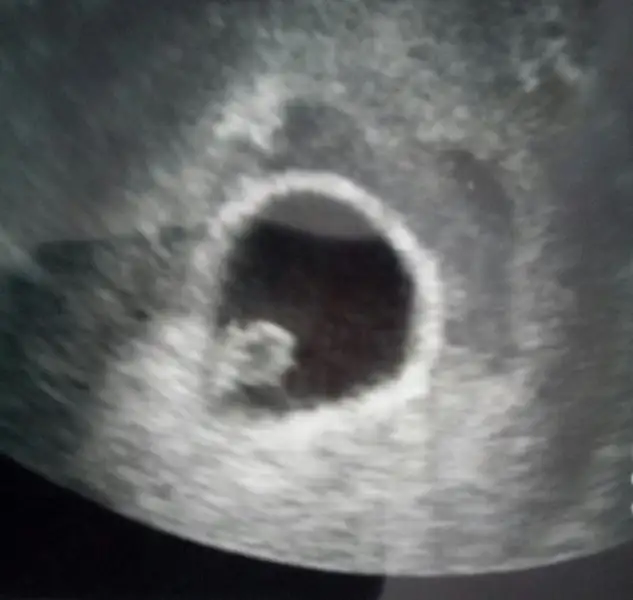

Mrb seninle aynı tarihteyiz anladığım kadarıyla dün gittim ilkkez dra hem bebiş hemde kalp atışı vardı genellikle 7. Haftada başlıyor zaten meraklanma duyacağına eminim

Kizlar sukurler olsun bebegimi gordum gorunce aglamaya basladim dedim kalbi atiyor mu doktor da kalbini birak baksana elini kolunu oynatiyor dedi masaAllah .Rabbim kimseyi boyle seylerle imtihan etmesin annelik ne zormus .gogus hassasiyeti gecebilirmis.doktor bulantin varsa korkma dedi.Normalde gogus hassasiyetiyle bulanti ayni anda gecermis ama senin biraz daha bulantin surecek gibi duruyor dedi.Bir mujde bekleyen herkes guzel.haberlere kavussun buradaki herkes saglikla bebeklerini kucagina alsin insaAllah